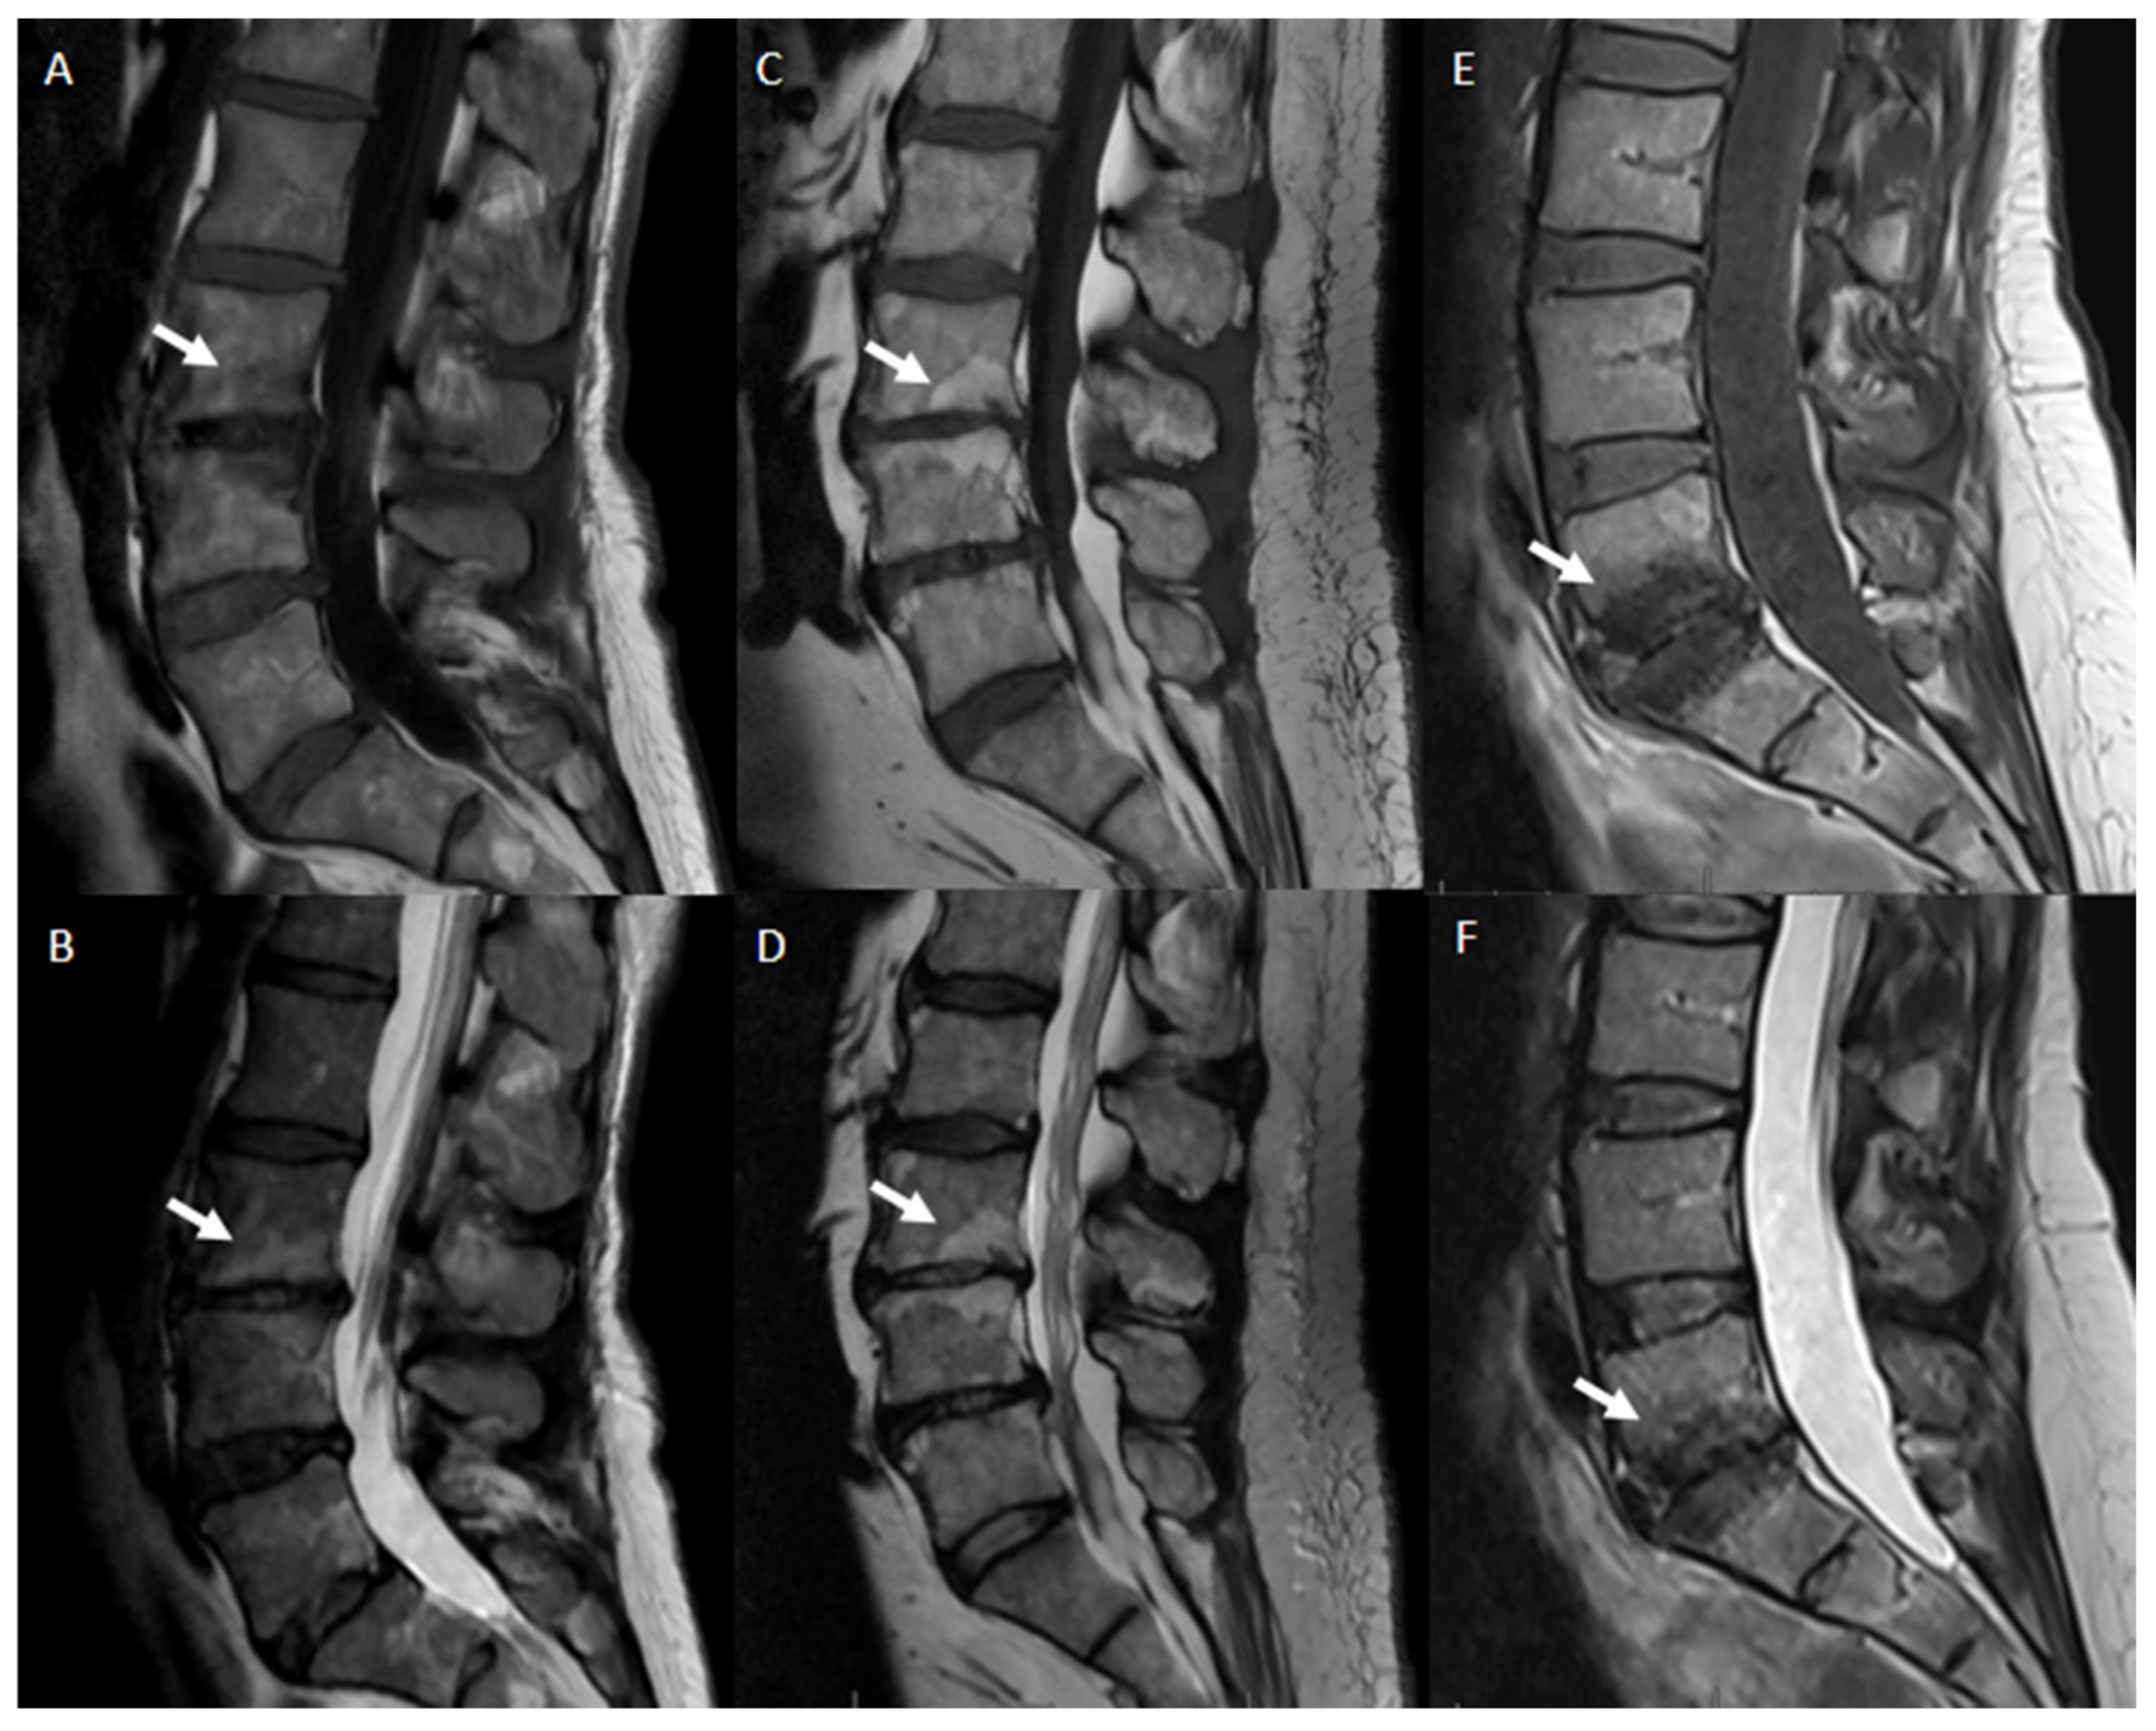

- Modic classification [16] is a classification for vertebral end plates and adjacent vertebral bodies MRI signal modifications secondary to disc inflammation and degenerative disc disease. Modic type 1 refers to decreased signal intensity on T1-weighted images and increased signal intensity on T2-weighted images. Such modifications may be chronic or acute and reflect the penetration of the end plate by fibrovascular tissue, inflammatory changes, and edema. Modic type II refers to increased signal intensity on T1-weighted images and isointense or increased signal intensity on T2-weighted images, indicating replacement of normal bone marrow by fat. Modic type III refers to decreased signal intensity on both T1- and T2-weighted images, indicating reactive osteosclerosis [55] (Figure 4).

| Type | T1 | T2 | Histopathology |

|---|---|---|---|

| 1 | Hypointense | Hyperintense | Bone marrow edema |

| 2 | Hyperintense | Hypointense | Fatty replacement |

| 3 | Hypointense | Hypointense | Sclerosis |